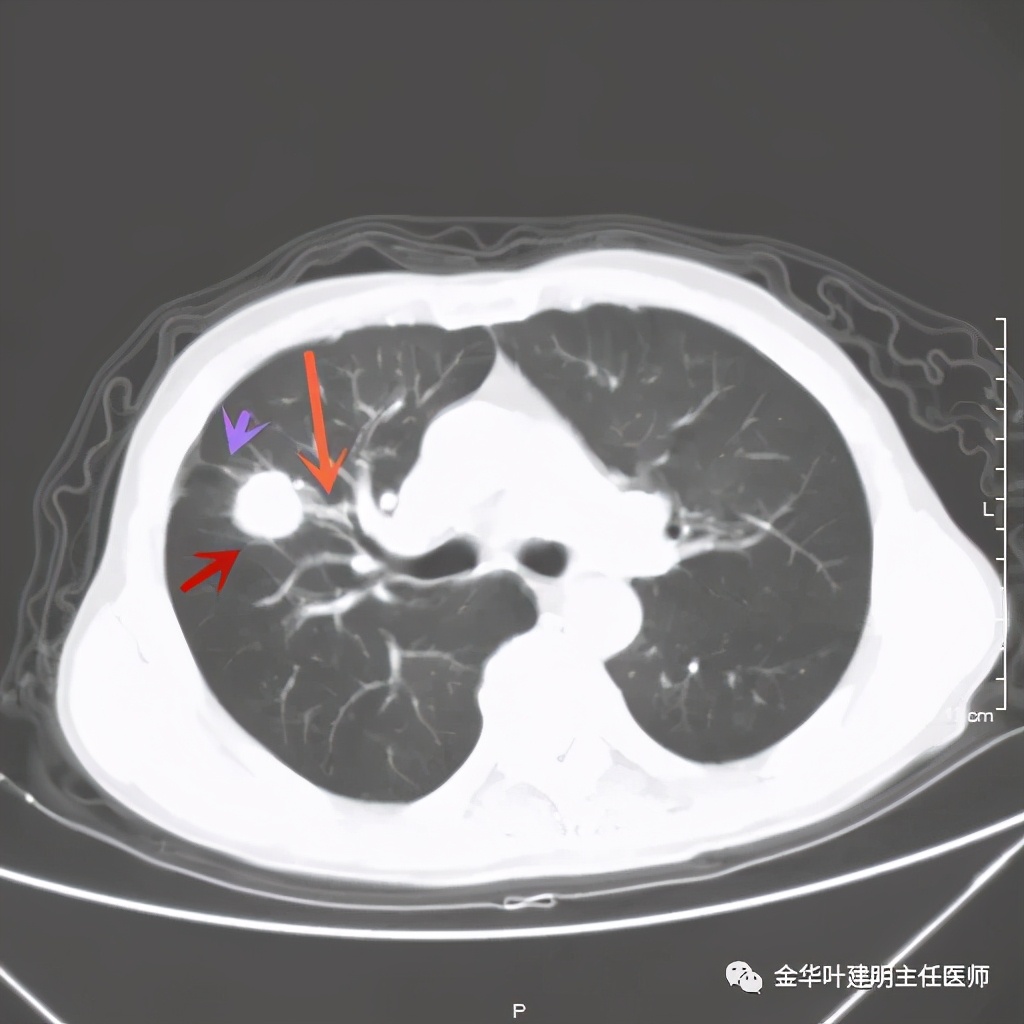

上图桔色箭头示血管进入病灶,较粗;紫色箭头示病灶与胸膜间似乎有所牵拉;红色箭头示病灶

上图紫色箭头示叶间胸膜受牵拉,病灶边缘部分见到细毛刺

上图是穿刺时的某个层面,病灶的细毛刺征比较明显(蓝色箭头),病灶的边缘是不平的,而且有细短的毛刺样突向周围肺组织,这可是恶性的特征

桔色箭头示病灶周围血管征明显,有较粗的血管进入病灶,较细的也有

上图紫色箭头示明显的叶间胸膜牵拉,红色箭头示病灶,中间还有空腔,边缘有细毛刺,感觉上病灶就是有收缩力而僵硬的

上图也见细毛刺,但不是特别广的范围,有的边缘还是相对比较光滑了点